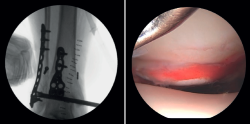

Colocación en el quirófano

En primer lugar, realizaremos el abordaje posterior, si lo requiere la fractura, y, tras reducir el maléolo posterior, colocamos al paciente en decúbito supino con una almohadilla debajo del glúteo. El tobillo debe ir colocado al borde de la mesa de quirófano, lo que permitirá la flexoextensión libre del tobillo, facilitando el manejo durante la artroscopia. La isquemia y los sistemas de aspiración e irrigación de agua los colocaremos al mismo lado de la fractura (pero puede variarse según las peculiaridades técnicas de cada hospital). La torre de artroscopia y el monitor del fluoroscopio cerca de la cabeza del paciente y, en el lado contralateral, colocaremos el arco en C en la parte inferior para optimizar la visualización y el acceso artroscópico y radiológico, permitiendo su uso de forma simultanea(7) (Figura 1 y Tabla 1).

- Valoración de la reducción del maléolo posterior: con la artroscopia podemos verificar la reducción del maléolo posterior(5) (Figura 2).